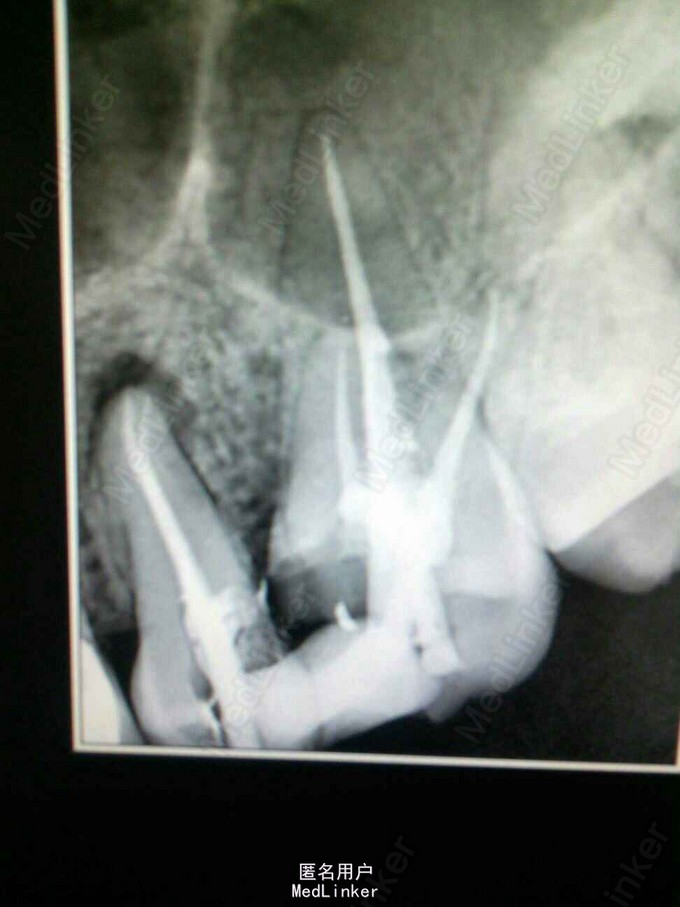

左上后牙根管治疗——25牙双根管,26牙四根管

25牙远中邻面,26近中邻面深龋 X片示25牙根尖暗影,26牙深龋及髓

25、26牙行根管治疗,25牙根下段分为双根管,26牙探及MB2,protaper预备根管,大锥度牙胶尖+AH糊剂充填,拍片恰填

protaper预备后的根管很漂亮,使用配套的大锥度牙胶尖单根充填就很严密